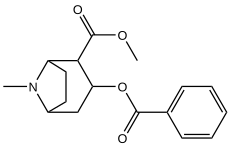

Леводопа

.svg.png)

Чёрная субстанция является главной целью химической терапии при лечении болезни Паркинсона. Леводопа (L-ДОФА), предшественник дофамина, является наиболее часто назначаемым противопаркинсоничесим препаратом. Особенно эффективна леводопа в лечении пациентов на ранних стадиях болезни Паркинсона, хотя препарат не теряет своей эффективности с течением времени[40]. Благодаря прохождению через ГЭБ, леводопа повышает уровень необходимого дофамина в чёрной субстанции, таким образом облегчая симптомы болезни Паркинсона. Недостатком лечения леводопы является то, что она устраняет симптомы болезни Паркинсона, при котором регистрируется низкий уровень дофамина, а не причину — смерть дофаминергических нейронов чёрной субстанции.

МФТП

МФТП (метилфенилтетрагидропиридин) — является нейротоксином, действующим на дофаминергические клетки головного мозга (имеет высокое сродство к дофаминовому транспортёру (DAT)[41]), в частности, в чёрной субстанции. МФТП стал широко известен в 1982 году, когда у небольшой группы людей из округа Санты-Клары (Калифорния, США) был диагностирован паркинсонизм после использования метилфенилпропиноксипиридина (МФПП), загрязненного МФТП. Нейротоксичность МФТП объясняется нарушением обмена веществ в митохондриях дофаминергических нейронов, в результате которого образуются свободные радикалы[42].

В 1984 году Лэнгстоном (Langston) и сотрудниками были проведены опыты, доказывающие прямое влияние МФТП на блокаду образования дофамина, приводящее к болезни Паркинсона. В настоящее время это вещество используется для моделирования болезни Паркинсона с целью её изучения и возможного лечения в лаборатории. Опыты на мышах показали, что восприимчивость к МФТП увеличивается с возрастом[43].